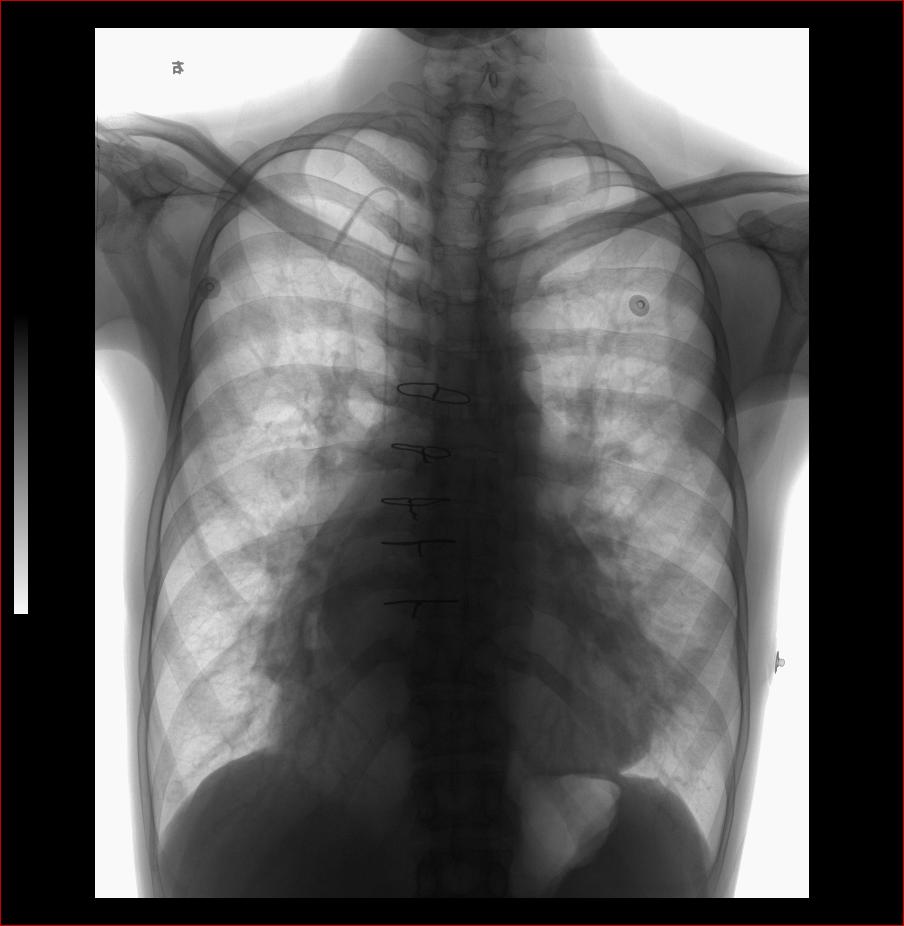

先天性心脏病、房间隔缺损

男31岁,心悸,气短

:主动脉结小,肺动脉突出,左心缘圆隆,右心房/心高值大,未见双房影,双肺呈多血改变,右下肺动脉宽。

符合先心病。心房间隔缺损。建议心彩。

结果

:患者既往彩超检查诊断,先心房缺